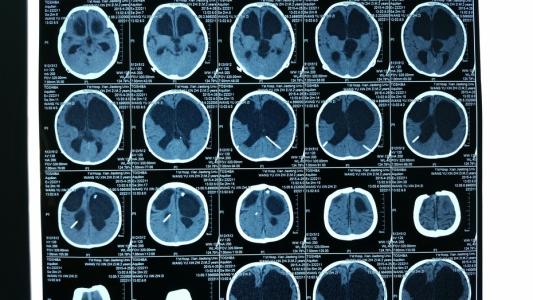

腦積水患者恢復以后需要注意的是觀察自己的頭痛,頭暈癥狀,不定期一般3~6個月復查一次顱腦CT,了解恢復情況,如果出現(xiàn)有頭痛劇烈或嘔吐等癥狀,有可能積水再次復發(fā)。

腦積水如果已經(jīng)完全治愈,那平時注意定期的復查,因為腦積水是有一定的復發(fā)幾率的,另外如果出現(xiàn)頭疼以及頭部的不適癥狀,需要及時的復查腦ct。注意正常的規(guī)律生活就可以了。